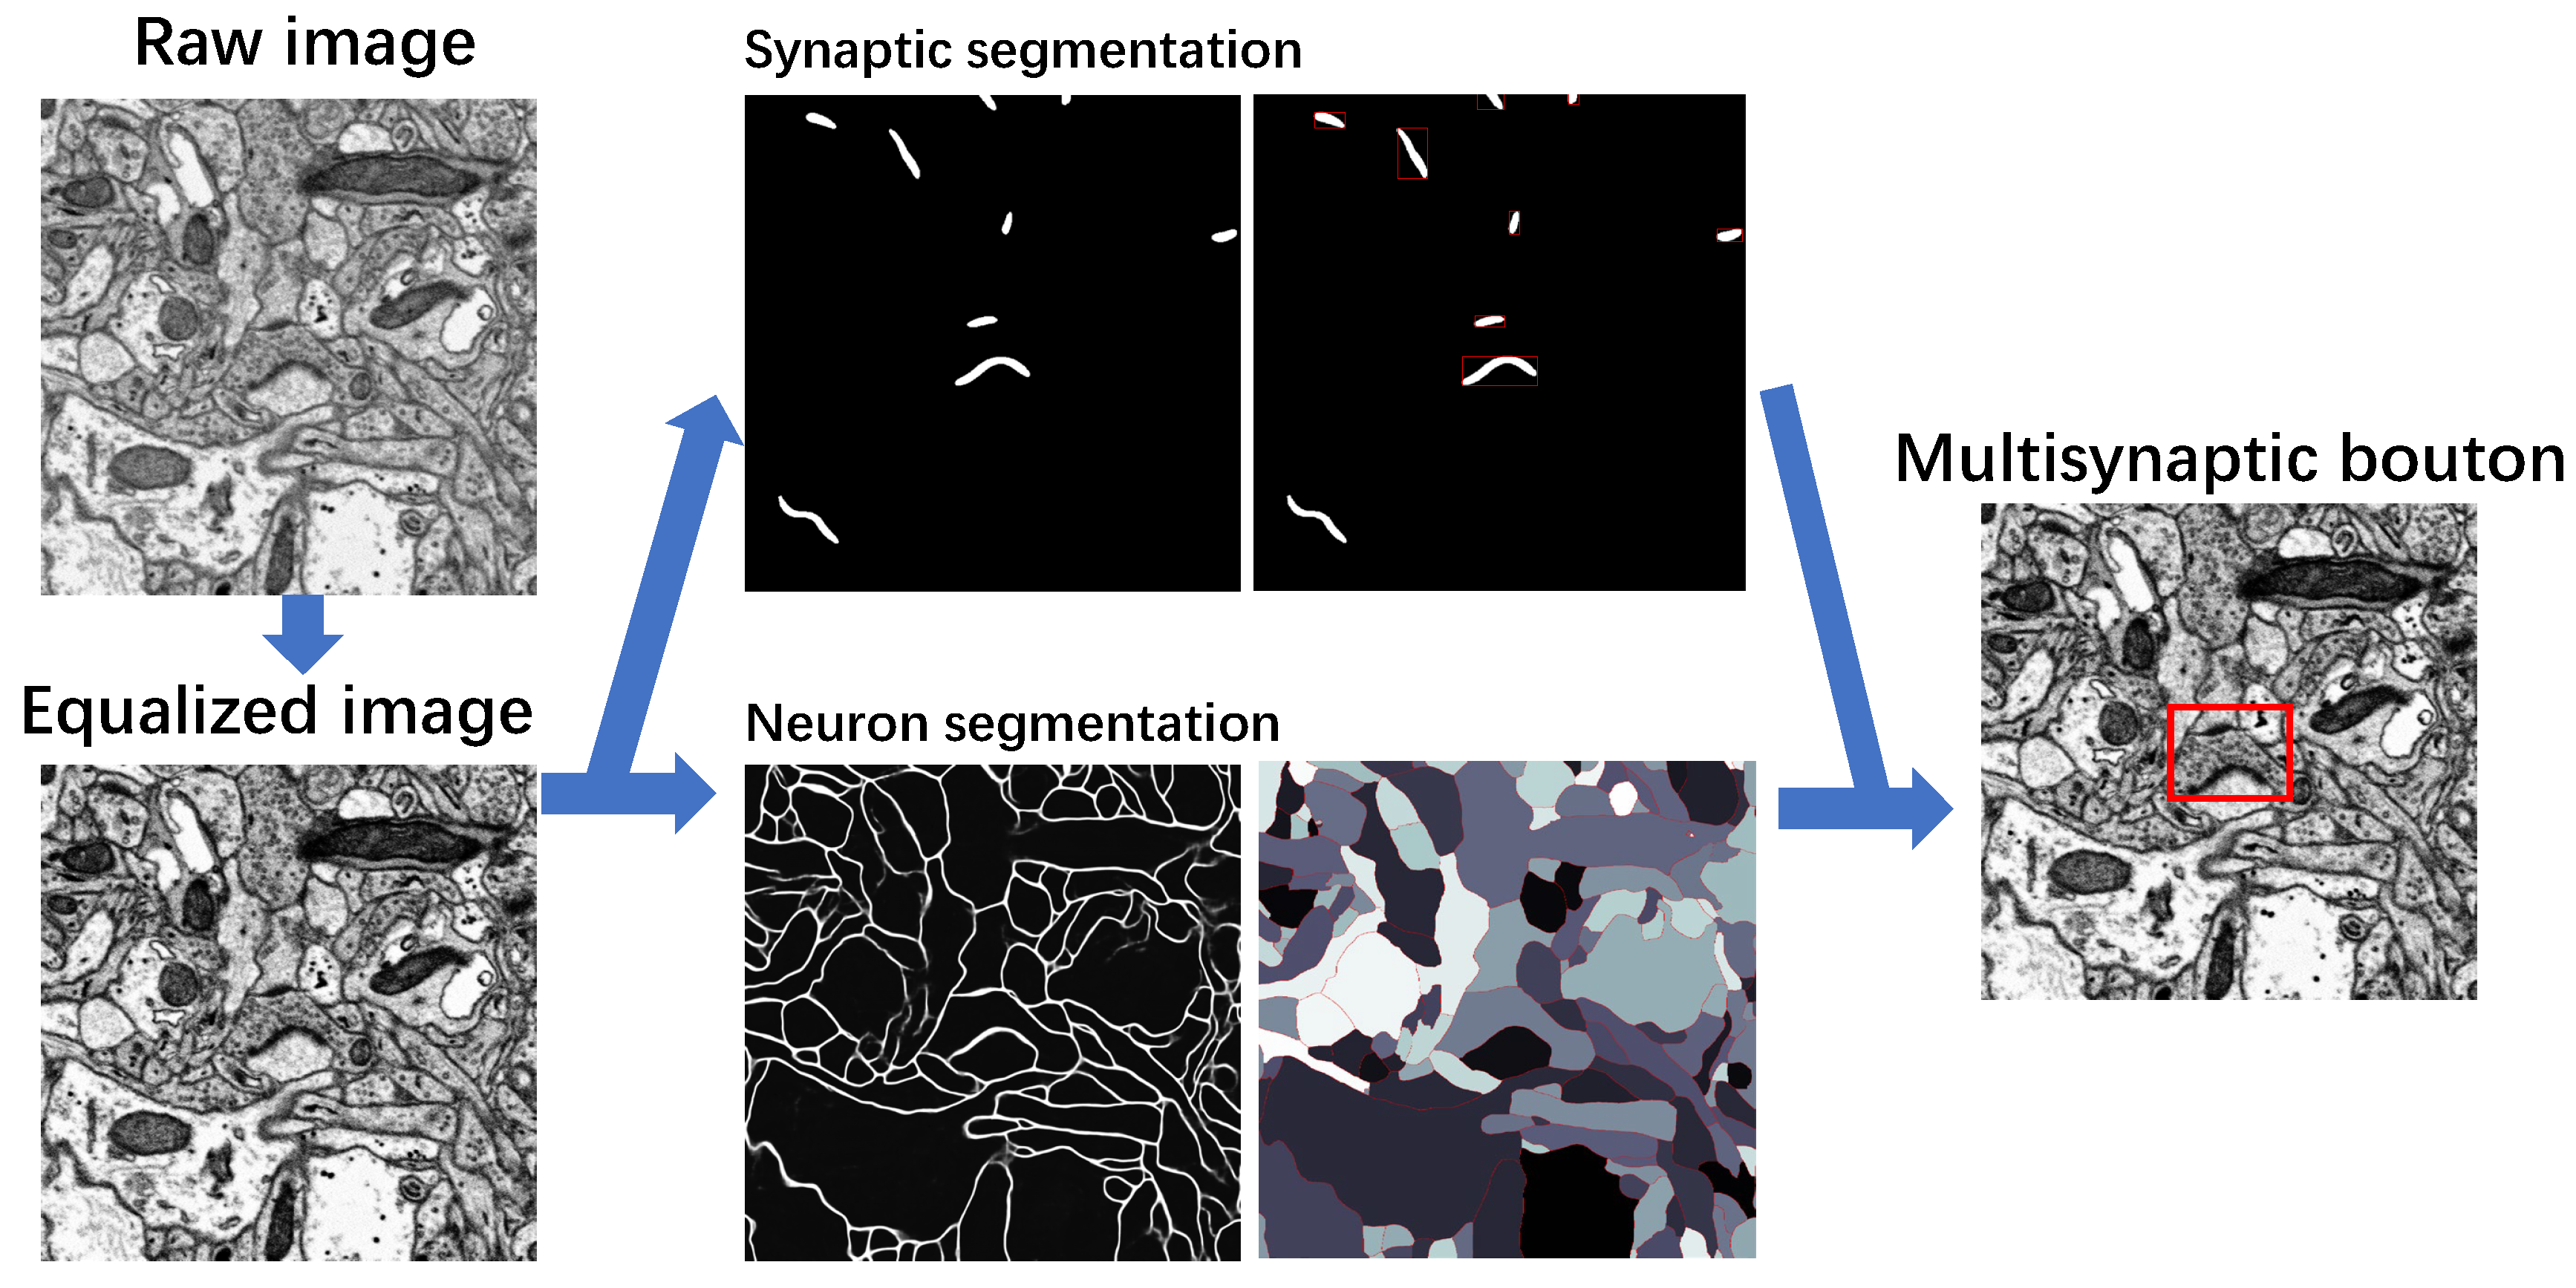

3. Methods

3.1. Image Preprocessing

3.2. Recognition of Synapse

3.3. Segmentation of Neuron

3.4. MSB Identification